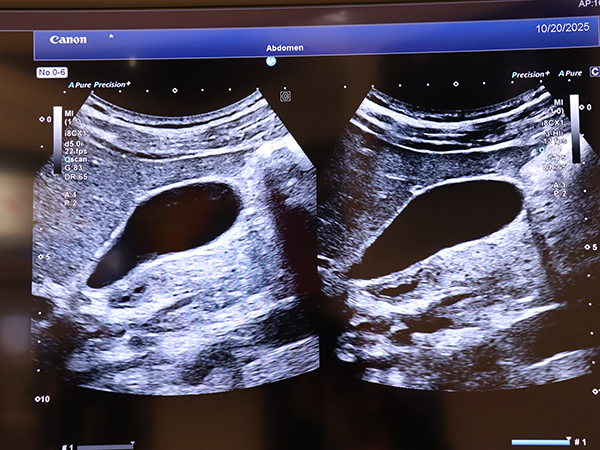

従来装置のTissue Harmonic Imaging(THI)では2次高調波を抽出して画像化しているのに対して,3-HIでは深層学習を利用してエコー信号から3次高調波のみを効率良く抽出することで,従来は画像化できなかった深部の組織を高解像度で画像化する。THIも浅部から深部まで良好な画像を描出するが,3-HIでは均一性がさらに向上し,診断に有用な画像を提供する。

「3-HI」(右)では管腔と組織の境界がよりシャープに描出され,管腔内の抜けもクリアになる